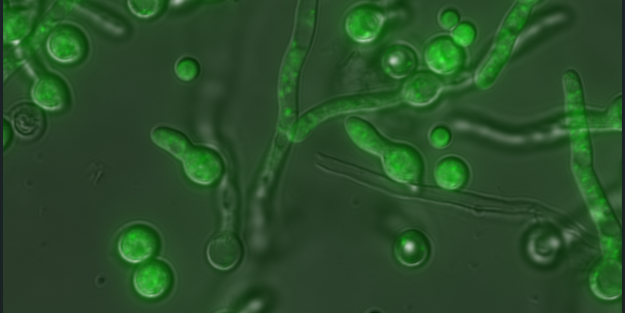

The team discovered that when the virus—a double-stranded RNA mycovirus—is present, the fungus becomes markedly more resilient to stress, including the heat and oxidative conditions found in the mammalian lung. Removing the virus from fungal strains made them weaker: virus-free fungi reproduced poorly, produced less melanin, and were significantly less dangerous in animal models.

Their findings suggest these “mycoviruses” have a crucial but previously overlooked role in worsening fungal diseases in humans. Particularly promising is the team’s observation that applying antiviral treatment to suppress the virus improved survival outcomes in infected animals. This opens a new avenue for antifungal therapy—not only targeting the fungus but also the virus that helps it thrive.